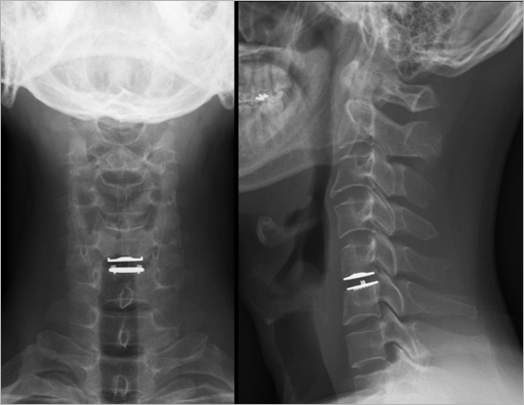

| 그림 4를 참조하여 추간판이 제거된 상태를 한 번 상상해 보십시오. 추간판이 완전히 제거되면 척추체와 척추체 사이가 일순간 빈 공간이 되어 버립니다. 이렇게 되면 추간판 공간이 주저앉게 되고 따라서 추간판 뒤쪽에 신경근이 빠져나가는 구멍도 좁아져서 수술을 통해 신경 조직을 누르던 추간판 돌출을 제거하더라도 신경근이 다시 눌릴 수 있습니다. 또한 척추 뒤쪽의 높이는 유지되는 대신 앞쪽이 가라앉아 목이 앞으로 굽어질 수 있습니다. 원래 정상 경추는 앞으로 볼록한 C자 형태의 완만한 곡선을 형성하고 있는데 목이 앞으로 굽어진다면 정상의 반대 곡선으로 변형될 수 있다는 것입니다. 이렇게 되면 위 아래 추간판에 가해지는 부하가 증가하고 척추 주위의 인대, 근육 등에 가해지는 부담도 늘어나 목의 통증도 나타날 수 있고, 경추의 노화 및 관절염을 가속화시킬 수도 있습니다. 물론 "추간판을 반드시 모두 제거해야 하는가? "허리 디스크"때처럼 돌출된 부위만 제거하면 되지 않는가?"라는 의문을 가지시는 분도 있을 것입니다. 일부 의사들은 목의 앞쪽을 통해, 혹은 내시경을 통해 추간판의 돌출된 부위만 제거하는 수술을 시도하고 있으나 아직까지는 그 효과와 안전성이 입증되지 않아 아직까지 국내외 대부분의 척추외과 의사들은 추간판 전체를 제거하는 수술 방법을 선호하고 있습니다. 다시 본론으로 돌아가 경추 인공디스크는 문제되는 추간판을 제거한 후 비어있는 공간에 삽입함으로써 기존의 추간판을 대신해 높이를 유지해 주고 움직임을 만들어 줄 목적으로 사용하게 되는 것입니다(그림 5). |

| • 그림 5 인공디스크 삽입술 환자의 엑스레이 사진 |

![]() |